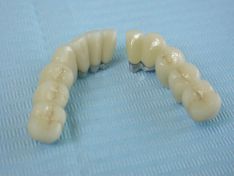

Intanto, si passa alla protesizzazione dell’intera arcata superiore con impronte in silicone, modellazione e fusione della struttura cerata in metallica di lega aurea, che successivamente verrà ceramizzata; (foto 25-26-27-28)

foto 25- 26

foto 27-28

Dopo un’accurata rifinitura, la struttura viene provata in arcata del paziente per eventuali modifiche ed accorgimenti di chiusura marginale sui monconi portanti .

In fine la struttura viene ceramizzata ed ottimizzata, per una corretta funzionalità estetica, fonetica e masticatoria.